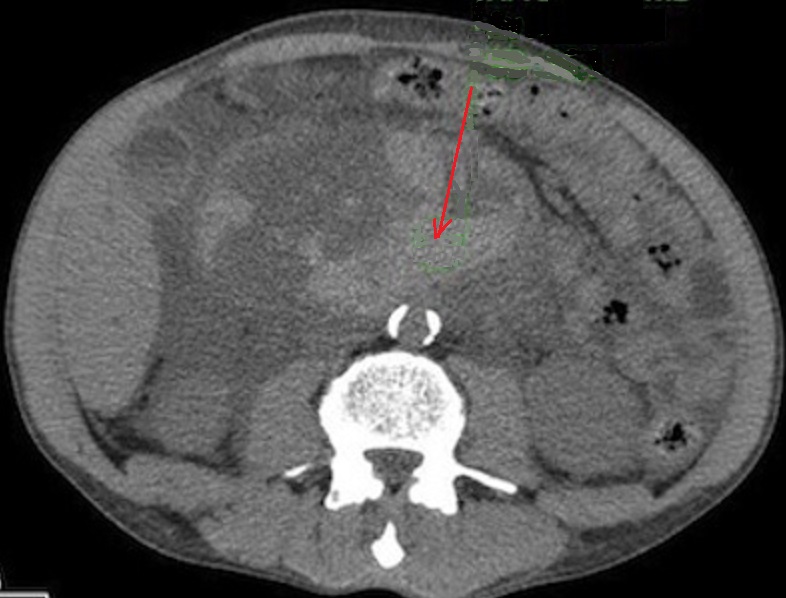

Image radiologique TDM d'une pseudo kyste du

pancreas a aspect lesionaire est un kyste arrondie

volumineuse a hypodense , a bord regulier , lisse ,

fine situe a la tete du pancreas ( fleche rouge ) .

Coupe TDM axiale |